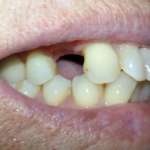

Viene proposta una terapia sostitutiva alla chirurgia implantare e alla protesi fissa convenzionale in un caso di assenza di elementi dentali. Le problematiche evidenziate hanno posto gli operatori clinici e tecnici di fronte alla necessità di valutare soluzioni che considerassero anche gli aspetti etici legati all’intervento su tessuti sani, evitando metodiche più invasive